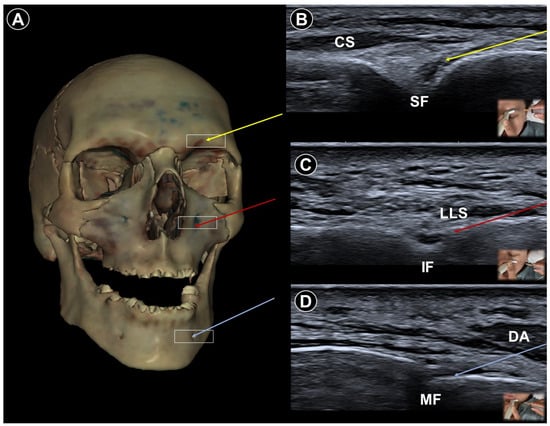

- Allam, A.E.; Khalil, A.A.F.; Eltawab, B.A.; Wu, W.T.; Chang, K.V. Ultrasound-Guided Intervention for Treatment of Trigeminal Neuralgia: An Updated Review of Anatomy and Techniques. Pain Res. Manag. 2018, 2018, 5480728. [Google Scholar] [CrossRef]

| Trigeminal neuralgia | Paroxysmal facial pain in one or more divisions of the trigeminal nerve | Neurovascular compression at root entry zone | Head neutral | Linear probe, in-plane

| Sustained pain relief by nerve block (case study) | Use Doppler imaging to avoid vascular puncture |

| Lateral, with affected side up | Curvilinear probe, out-of-plane